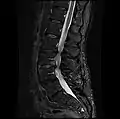

MRI lumbar spine with degeneration, post-hemilaminectomy L4-5 (sagittal FAST STIR)- MRI lumbar spine post-hemilaminectomy (sagittal T2 FRFSE)